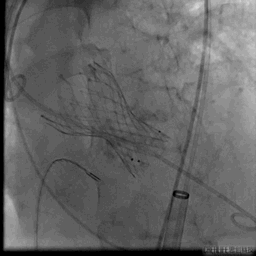

瓣膜完全释放

术后

跨瓣压差消失,无瓣周漏,手术效果良好,术后一周顺利出院。